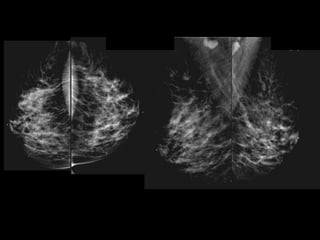

HISTORY

• 61 yo female

• Strong family history of breast and ovarian

cancer

• Presents for routine screening

mammography

• What is the abnormality?

• What is your differential diagnosis?

• What are your recommendations?